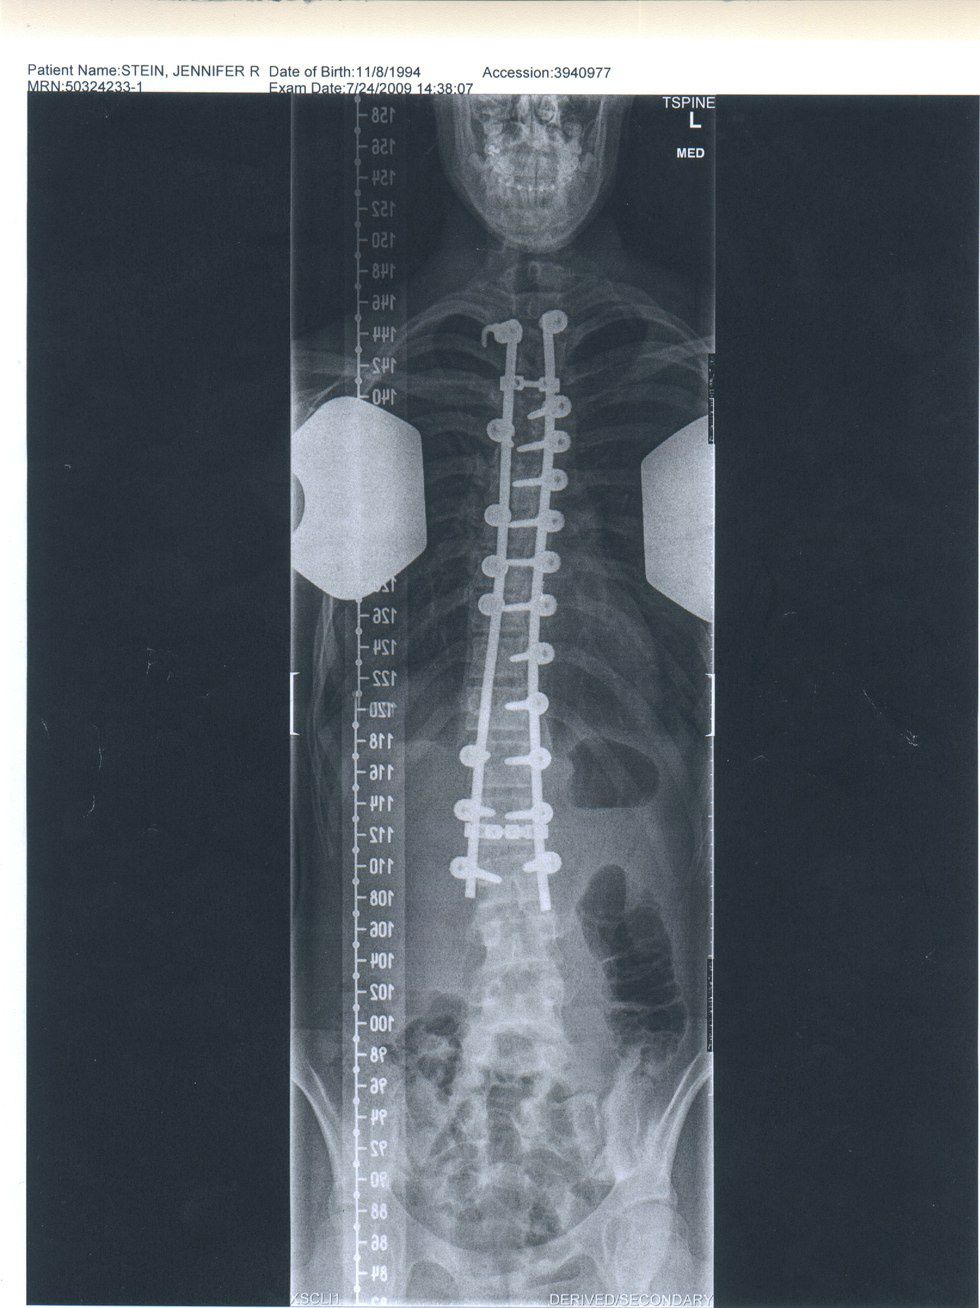

The scoliosis was painful, my body didn't function the way it used to. My muscles always ached and my ribs stabbing my lungs. I knew I wanted to have the surgery, and I decided right there that I wanted the surgery as soon as possible so I could play sport by my senior year of high school. The surgery consists of attaching titanium rods to my spine with surgical screws.

It all happened so fast. The pain in the fall, the diagnosis in the winter, and by spring I had my operation physical, I had blood drawn for the dialysis machine I would be hooked up to to keep my blood running during my surgery, and my last x-rays before the surgery. My curvature had increased to 55 degrees. In less than a year I had never heard of scoliosis and then I was having a incredibly risky surgery.

My time in the hospital was interesting. There was a lot of not sleeping that occurred, as I was checked on my a nurse every two hours. They needed to make sure I had enough meds, and to make sure I could still feel all of my limbs. The night the day after my surgery, I was whisked away to have a CAT scan, and the news we got back from the doctors was not good. They had put three of the screws in my lower vertebrae not the correct angle. I needed to have a second surgery. So on the 17th of July, I remember they disconnected me from my morphine drip and knocked me out for a second five hour surgery.

[Note: the "ooops" written in by the doctors]